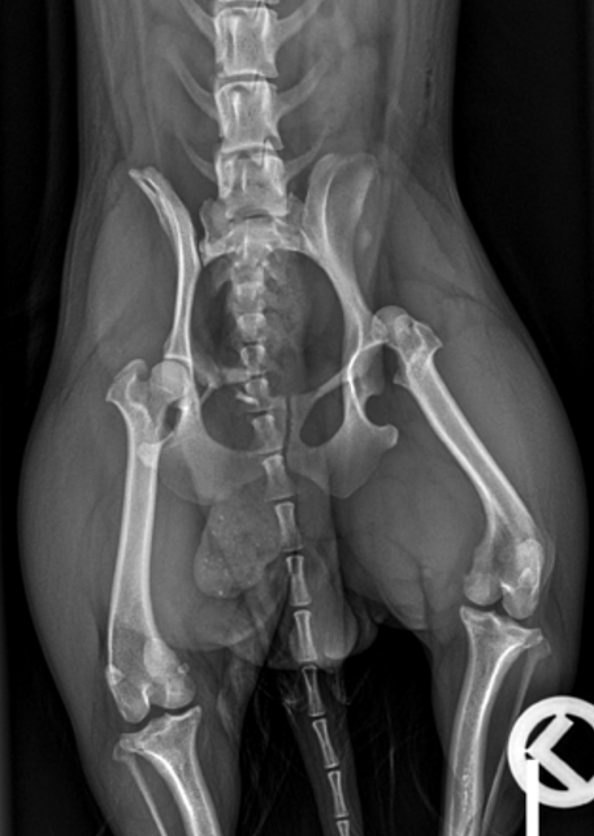

Anbei die Röntgenbilder der Hündin Gina. Gina ist eine weiblich kastrierte 1-jährige Mischlingshündin und wurde bei uns aufgrund einer Lahmheit nach Trauma vorstellig. Welche Pathologien erkennen Sie und welches weitere Vorgehen empfehlen Sie?

Auf der lateralen und ventrodorsalen Aufnahme des Beckens ist eine segmentale Fraktur des rechten Os pubis erkennbar. Es sind drei Frakturstellen identifizierbar (blaue Pfeile), eine zwischen Corpus ossis pubis und Ramus cranialis, die möglicherweise unvollständig ist. Eine weitere Fraktur im Ramus cranialis ossis pubis und die letzte zwischen Ramus cranialis und Ramus caudalis ossis pubis. Aus dieser Fraktur entstehen zwei Fragmente, von denen eines nahe dem Corpus ossis pubis liegt und geringgradig nach kranial verschoben ist, während das andere frei in den Weichteilen liegt und zwischen den beiden Frakturen zentriert ist. Die Konturen der Frakturen sind alle scharf abgegrenzt, was auf ein akutes Trauma hinweist. Die Symphisis pubis scheint leicht nach links lateral verschoben zu sein. Um eine Verschiebung des Beckens zu ermöglichen, sind drei orthogonale Frakturen erforderlich, die auf diesen Röntgenbildern nicht erkennbar sind.

Der rechte Femurkopf ist vollständig aus dem Acetabulum luxiert und nach kranial und dorsal verschoben (blaue Kreise). Die Weichteile des linken Femurs sind geringgradig verdickt. Im linken lateralen Aspekt der abdominalen Wand ist eine minimale Luftansammlung erkennbar. Beidseits sind die Coxofemoralgelenke geringgradig nach außen rotiert, welches eine laterale Positionierung der Patellae verursacht. Im rechten Kniegelenk befindet sich die Patella jedoch in medialer Position (blauer Pfeilkopf). Es ist unklar, ob ob diese traumatisch oder rasse-bedingt entstanden ist und welcher Grad der Patellaluxation vorliegt. Die sichtbaren caudalen abdominalen Organe sind ohne besonderen Befund.

Es handelt sich um eine akute, geschlossene, monostotische, segmentale Fraktur des rechten Os pubis, eine kraniodorsale Luxation des linken Femurs, eine mediale Luxation der rechten Patella und eine geringgradige Weichteilschwellung des linken Oberschenkels.